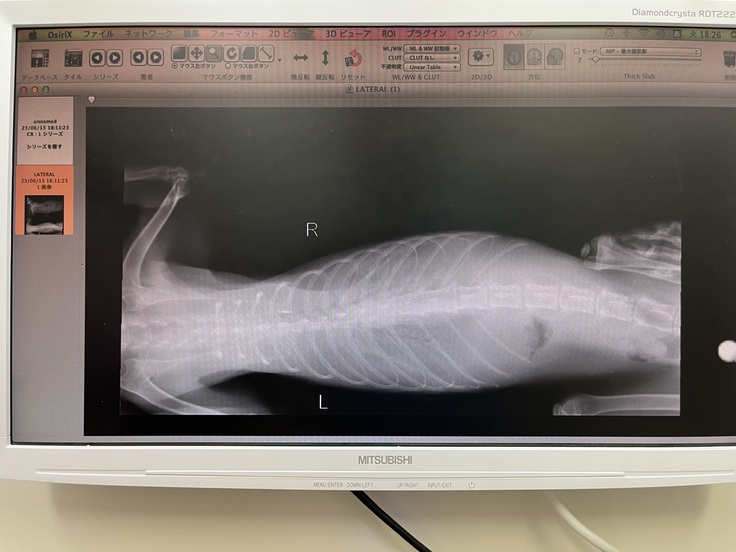

胸水がとても溜まっているとの事ですぐに処置をして頂きました。

※その日に抜いてもらった胸水とレントゲン写真です。

6月13日

そこでFIPかもしれないと診断されました。

血液検査と胸水での遺伝子検査をしてもらいやはりFIPだという確定診断されました。

その中でなつめはウェットタイプでした。